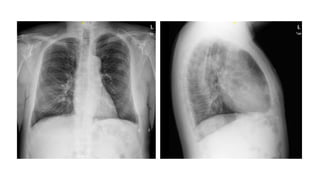

Pruebas complementarias

- ECG: Ritmo sinusal con FC 102lat/min. PR 230ms.

- RX de tórax: